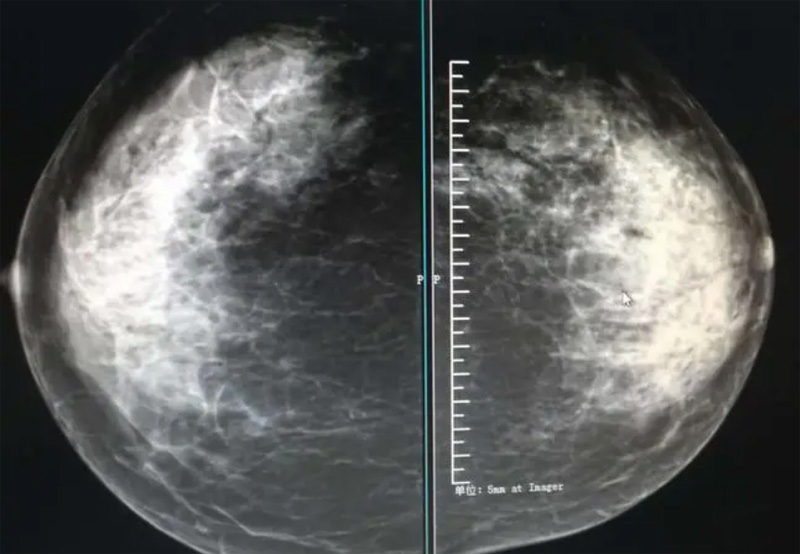

乳腺DR攝影體位有頭尾位及內外側斜位,

乳房在片子的中央,乳頭切線位,可見小部分胸大肌,內側乳腺組織應全部包括在片中,外側乳腺組織盡可能包括在片中。一張好的MLO位圖像顯示如下:乳房被推向前上,乳腺實質充分展開,胸大肌可見,較松弛,下緣達到乳頭水平,乳頭在切線位,部分腹壁包括在片中,但與下部乳腺分開,絕大部分乳腺實質顯示在片中。乳腺組織外緣可見乳頭的輪廓;乳腺后方的脂肪組織被很好地顯示出來,乳房無皺褶。對于CC位及MLO位顯示不良或未包全的乳腺實質,可以根據病灶位置的不同選擇以下體位:外內側位(LM)、內外側位(ML)、內側頭尾軸位(MCC)、外側頭尾軸位(LCC),尾葉位(CLEO)及乳溝位。在臨床實踐中,對于常規體位上發現的異常改變,可以進一步采取一些特殊的攝影技術,包括局部加壓攝影、放大攝影或局部加壓放大攝影技術。

2、規范觀圖程序:屏幕軟閱讀或在專用日光觀片燈下膠片閱讀,后者應同時準備白熾強光燈及觀片放大鏡。注意雙側乳腺配對觀察,推薦雙眼橫向掃描,進行雙乳相同部位圖像比較分析。

3、乳腺實質背景的確定:觀察乳腺實質與脂肪的構成比例,了解乳腺實質類型,以判斷對某些乳腺攝影征象敏感性的影響,有利于確定乳腺攝影對疾病的診斷價值。

必須指出的是,美國放射學會提出的乳腺影像報告和數據系統(Breast Imaging Reporting and Data System, BI-RADS)將乳腺分為4型:脂肪型(乳腺內幾乎全部為脂肪組織,腺體組織占25%以下)、少量腺體型(乳腺內散在腺體組織,大約占25%~50%)、多量腺體型(乳腺呈不均勻致密表現,腺體組織大約占51%~75%)、致密型(乳腺組織非常致密,腺體組織占75%以上)。這種分型的主要意義在于說明X線對不同乳腺類型中病變檢出的敏感性不同,對發生在脂肪型乳腺中病變的檢出率很高,而對發生在致密型乳腺中病變的檢出率則有所降低,臨床醫師了解這一點很重要。